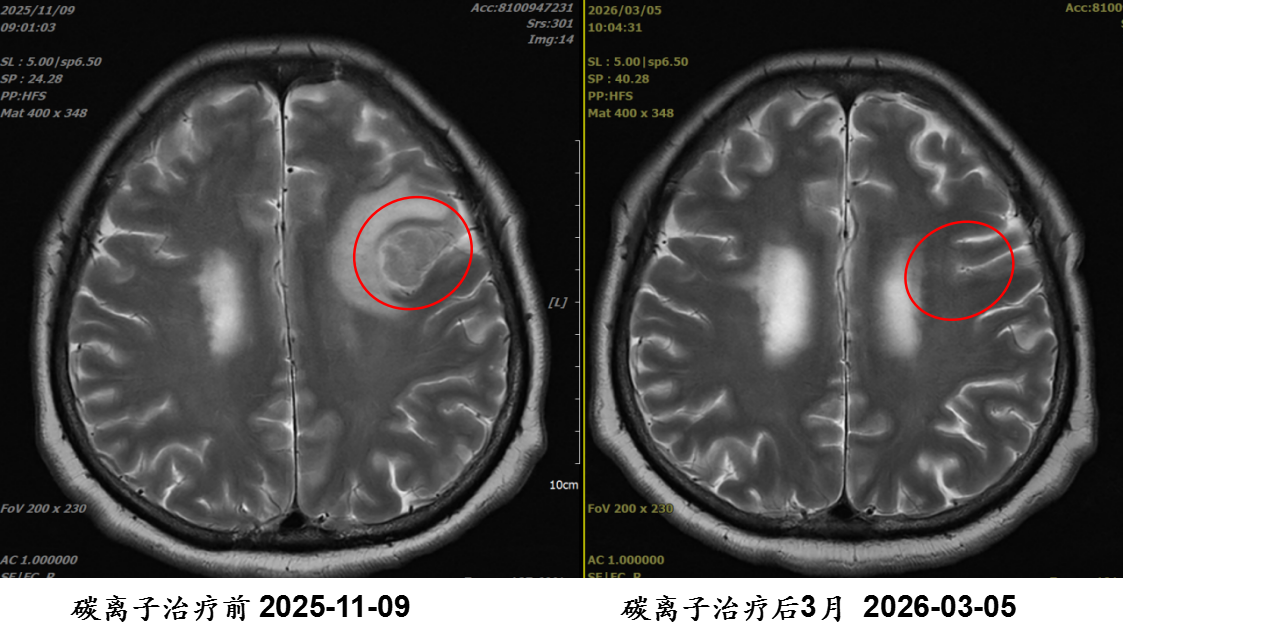

刘某某,女,56岁;主因“肺癌伴脑转移重(碳)离子治疗后3年余,左上肢无力1年余”入院; 诊断:1.右肺下叶恶性肿瘤(靶向、γ刀及碳离子治疗后) 腺癌 cT4N0M1c IVB期 2.脑继发恶性肿瘤; 重(碳)离子治疗:左侧额叶转移病灶重(碳)离子治疗。

病例提供医生:杨钰玲 科室:放疗中心一科(国际一部)